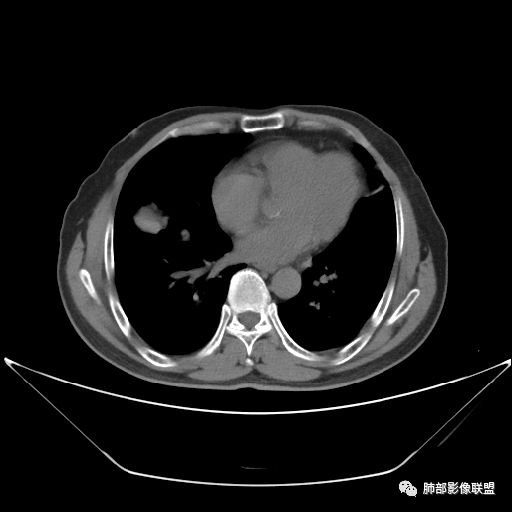

住院4天后行胸部增强CT

动脉期

老年男性,因“咳嗽咳痰1月余。”入院。病程中咳嗽咳痰,咳黄白痰,间断咯少许鲜红色痰血。PPD阳性。胸CT:右肺中叶外侧段支气管管腔阻塞,大片实性病变,病灶边缘光滑,部分边缘膨隆,可见分叶,肺门及纵隔可见肿大淋巴结,并可见钙化。增强可见病灶明显强化,而且延迟强化明显,病灶内多发低密度区,内见血管影,血管变细、部分血管破坏。考虑恶性病变可能性大,鉴别慢性肉芽肿性病变。

胸CT:跨叶大肿块,主体在中叶,右中叶外侧段支气管阻塞,病灶部分边缘膨隆,可见分叶,部分边缘平直,肺门及纵隔可见肿大淋巴结。增强病灶不均匀强化,延迟强化明显,病灶内多发低密度区,内见血管飘浮,部分血管变细、模糊。考虑:恶性病变可能性大,大细胞?淋巴瘤?鉴别慢性肉芽肿性病变。

右肺中叶软组织肿块,外围向内生长,叶间胸膜向前内移位,肿块近肺门侧跨叶,中叶外侧段支气管截断,密度不均匀,双侧肺门及隆突下见肿大淋巴结,增强后呈中度不均质强化,肺动脉供血,多发坏死区,边界尚清,坏死区域内见结构,结合病史考虑恶性,鉴别诊断1结核,爬行征是沿支气管树分布,外宽,内窄,周围有卫星灶,内气管狭窄后扩张,此例沿叶间胸膜长轴分布,气管有截断,不典型。2炎性肉芽肿,符合的地方下方层面增强后延迟性轻度环形强化,不符临床无发热等急性感染病史,实验室指标不符,病灶周围渗出及慢性炎性改变有,不明显。